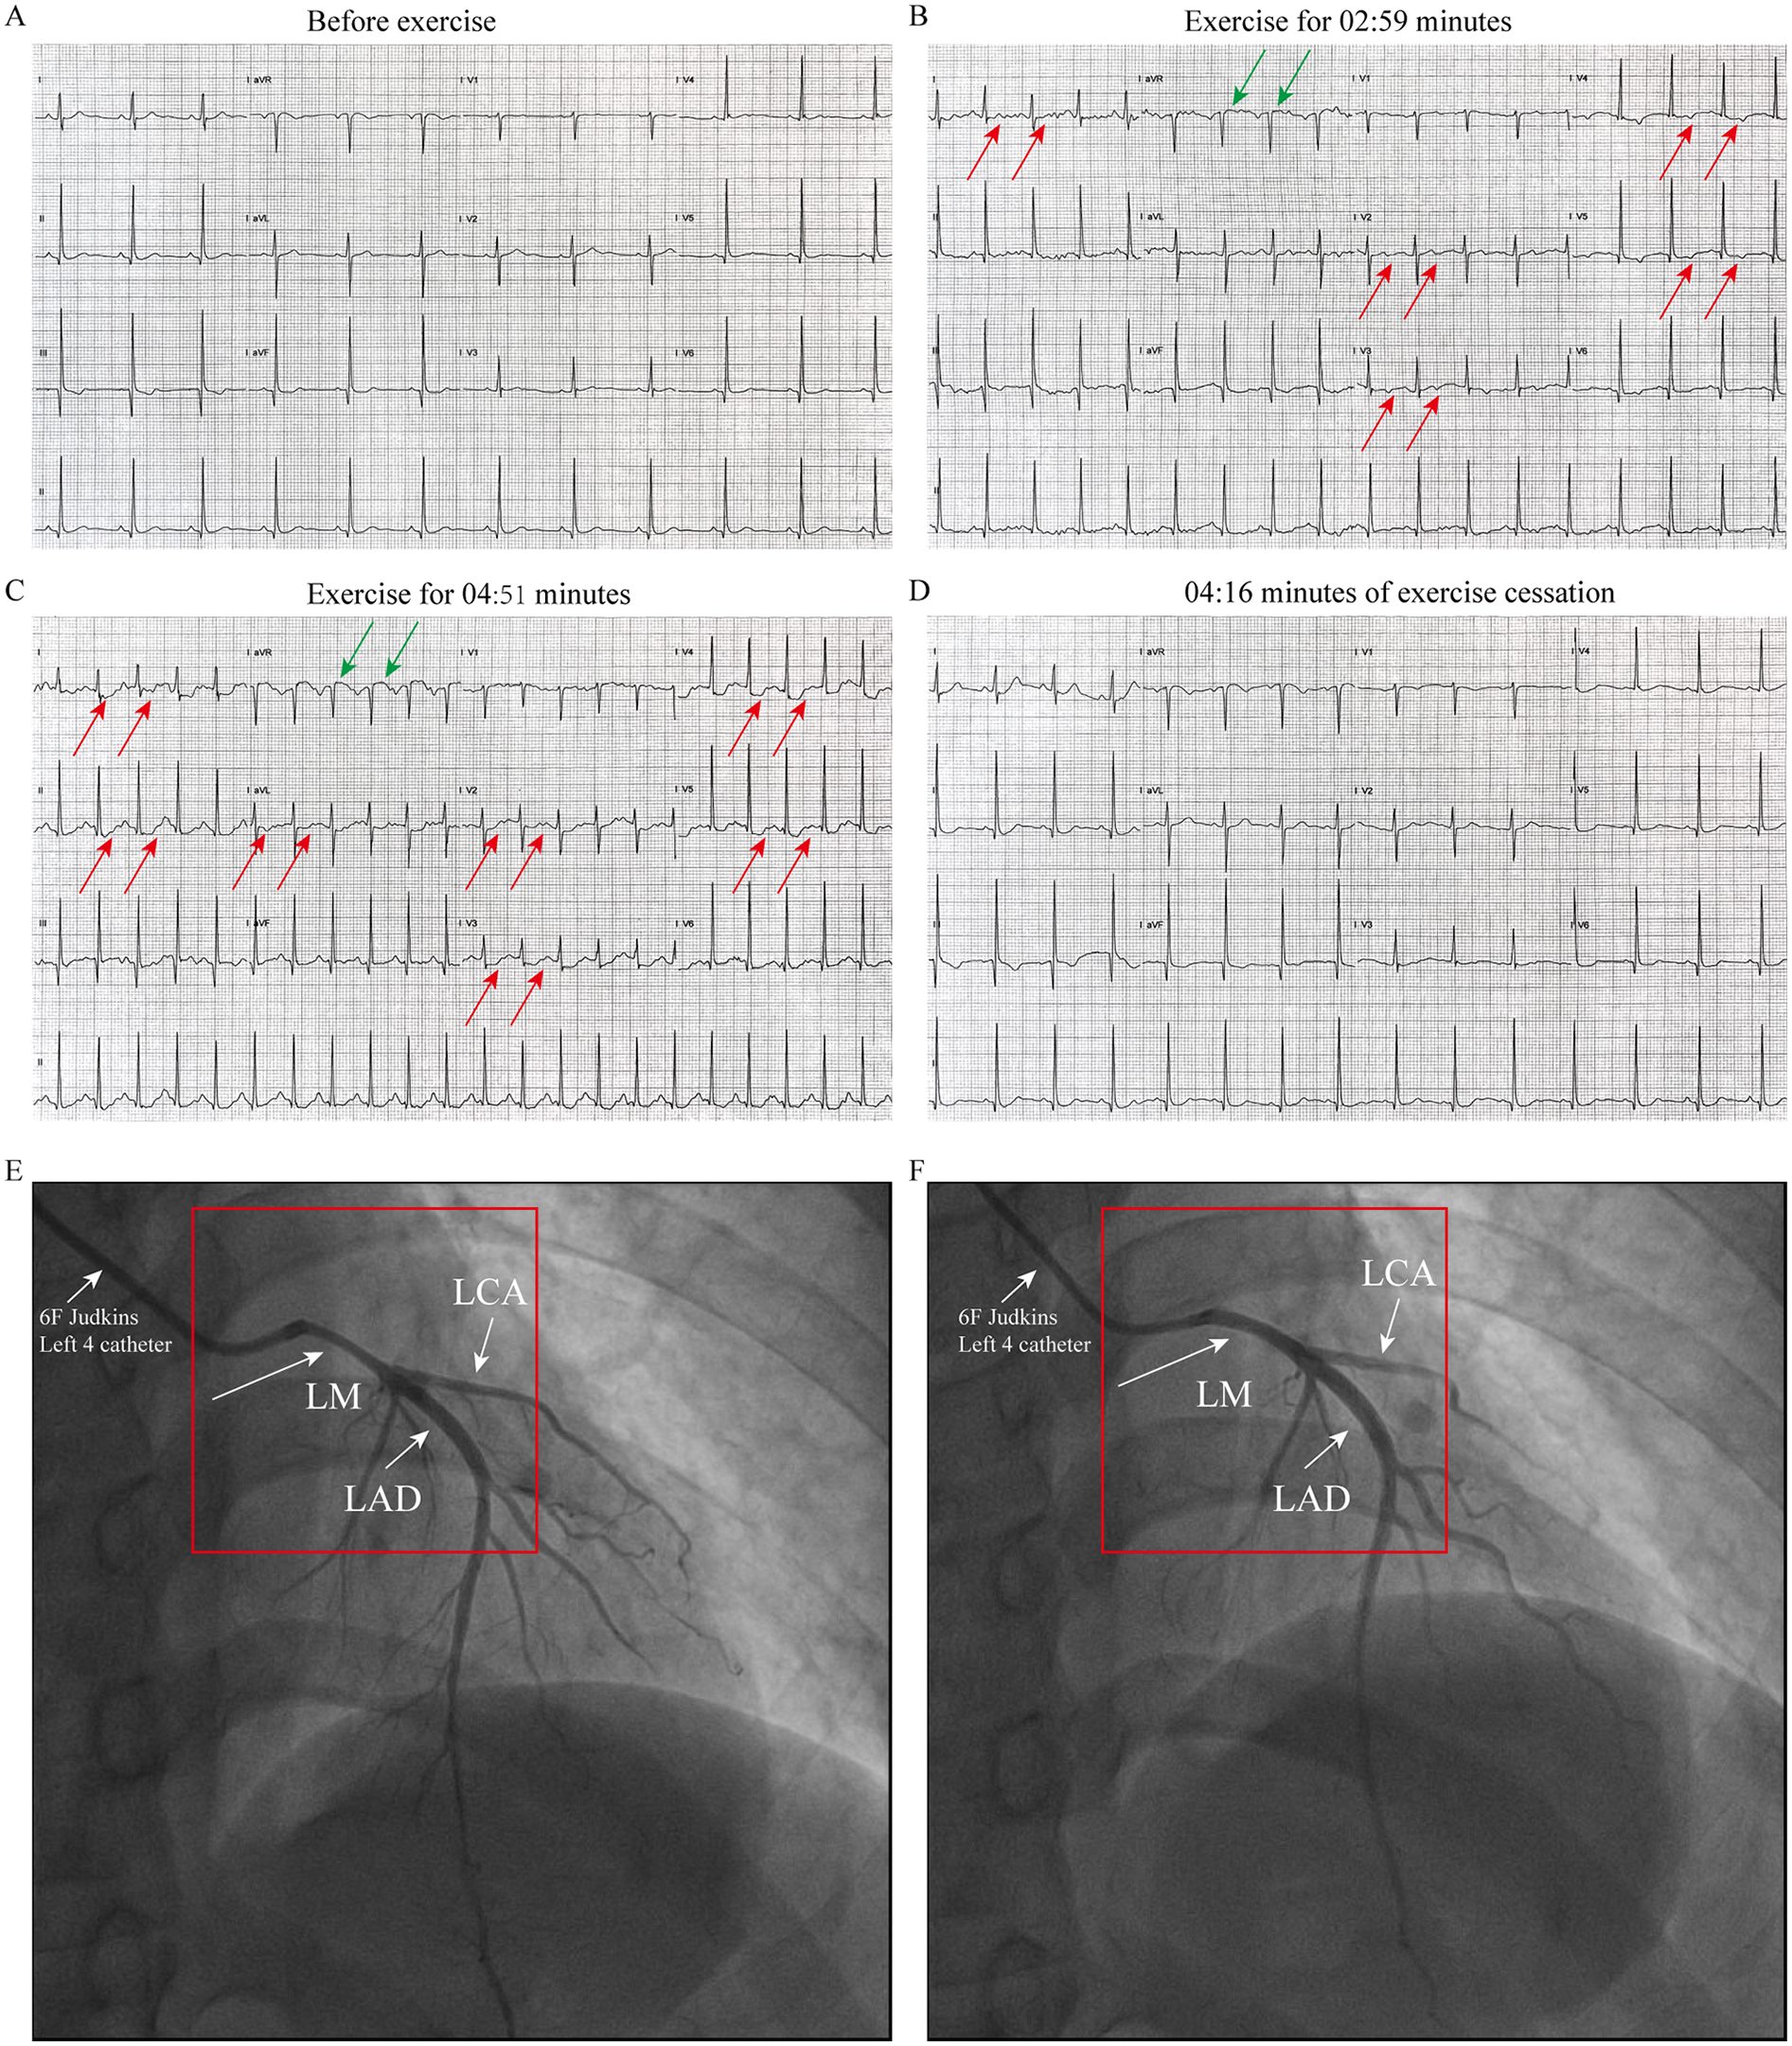

Patient 1 (Younger Sister): A 39-year-old woman was admitted in March 2025 for evaluation of recurrent episodes of chest pain. Each episode lasted approximately 10 min and resolved spontaneously. Her symptoms had intensified in the week preceding admission. She had no conventional cardiovascular risk factors for coronary artery disease (Supplementary Table 1). Vital signs and physical examination were unremarkable. Laboratory evaluations—including complete blood count, cardiac enzymes, troponin, liver and renal function tests, and lipid profile—were all within normal limits. Upon admission, the patient underwent a treadmill exercise test. The electrocardiogram (ECG) before exercise was nearly normal (Figure 1A). During the treadmill exercise test, the following findings were observed: After 02:59 min of exercise, ECG only showed mild ST-segment elevation in lead aVR and T-wave inversion and mild ST-segment depression in lead I and V2-V5(Figure 1B). By the 04:51-min mark, the patient developed chest pain, along with ST-segment elevation in lead aVR and persistent ST-segment depression in lead I, II, aVL, and V2–V5 (Figure 2C). All symptoms and ECG abnormalities resolved 04:16 min after cessation of exercise (Figure 2D). Coronary angiography demonstrated approximately 60% spasm in left main coronary artery, left circumflex branch artery and left anterior descending artery (Figure 1E) and a normal right coronary artery. The administration of 200 µg intracoronary nitroglycerine resulted in prompt relief of the spasm, with restoration of normal luminal diameter and coronary flow (Figure 1F). Her symptoms resolved completely under calcium channel blocker therapy, and she was subsequently discharged in stable condition.

Figure 1

ECG and coronary angiography findings of case1: (A) baseline ECG (pre-exercise). (B) ECG at 02:59 min of exercise, demonstrating mild ST segment elevation in lead aVR and T-wave inversion and mild ST segment depression in lead I and V2–V5 (indicated by the arrow). (C) ECG at 04:51 min of exercise, showing ST segment elevation in lead aVR and persistent ST-segment depression in lead I, II, aVL, and V2–V5 (indicated by the arrow). (D) At 04:16 min cessation of exercise, ECG abnormalities resolved. (E) Coronary angiography performed with a 6F catheter reveals about 60% stenosis in the left main coronary artery (LMCA), left circumflex artery (LCX), and left anterior descending artery (LAD), as indicated by the arrow. (F) After resolution of spasm with TIMI III flow after intracoronary nitroglycerin administration (Indicated by the arrow).